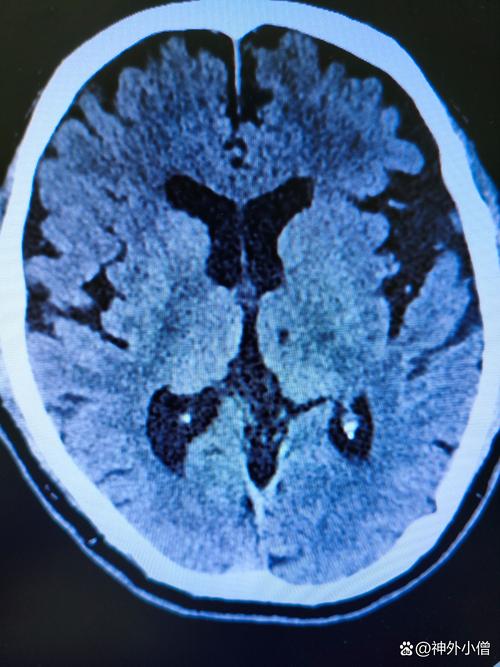

- 脑萎缩:大脑体积会自然地、缓慢地缩小,脑沟会变深,脑室会轻度扩大。

- 白质变性:大脑内部负责连接不同神经纤维的“白质”会出现一些轻微的缺血性改变,在影像上表现为一些片状的、边界不清的信号异常,这和脑小血管病有关。

- 与“腔梗”的关系: “老年脑”是“腔梗”和“缺血灶”发生的土壤,随着年龄增长,血管会自然老化,加上高血压、糖尿病等危险因素的长期作用,使得老年人更容易出现脑小血管的病变,从而产生腔梗和缺血灶,这三者常常同时出现,互为因果。